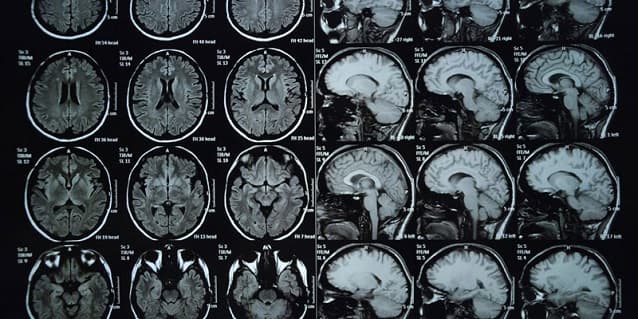

Chụp cắt lớp vi tính cung cấp hình ảnh chi tiết về xương, mô và mạch máu

Việc chụp cắt lớp vi tính cung cấp hình ảnh chi tiết về xương, mô và mạch máu. Các hình ảnh này rõ nét và cụ thể hơn chụp X quang thông thường. Phương pháp này cho kết quả chính xác cao. Vì vậy, đây là một phương thức chẩn đoán hình ảnh được lựa chọn trong các trường hợp cần chẩn đoán nhanh, đặc biệt là cấp cứu.